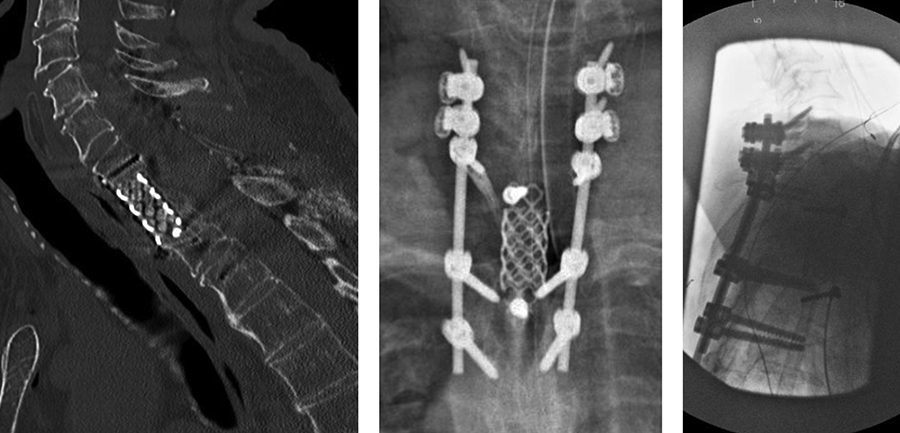

· C5-T3 posterior instrumentation with the DePuy Synthes SYMPHONY OCT System. Given the patient’s suboptimal bone quality, C5 and C6 lateral mass screws were reinforced with two MULTIPOINT SECURE screws placed bilaterally for an additional eight screws (Fig 7).

The patient had immediate relief of the radicular symptoms postoperatively. Three months postoperatively (Fig 8), he had no neck pain and was anxious to return to daily exercise at the gym. He had maintained resolution of his radiculopathy and was satisfied with the outcome.